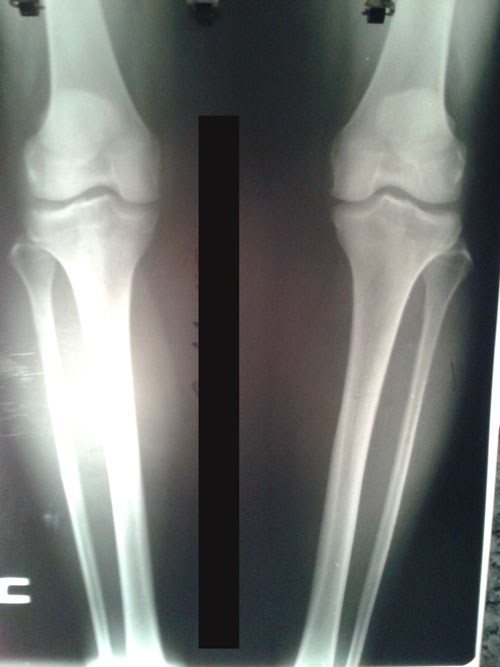

Ножки на сегодня.

Пациентка делает упор на правую ногу, левую щадит.